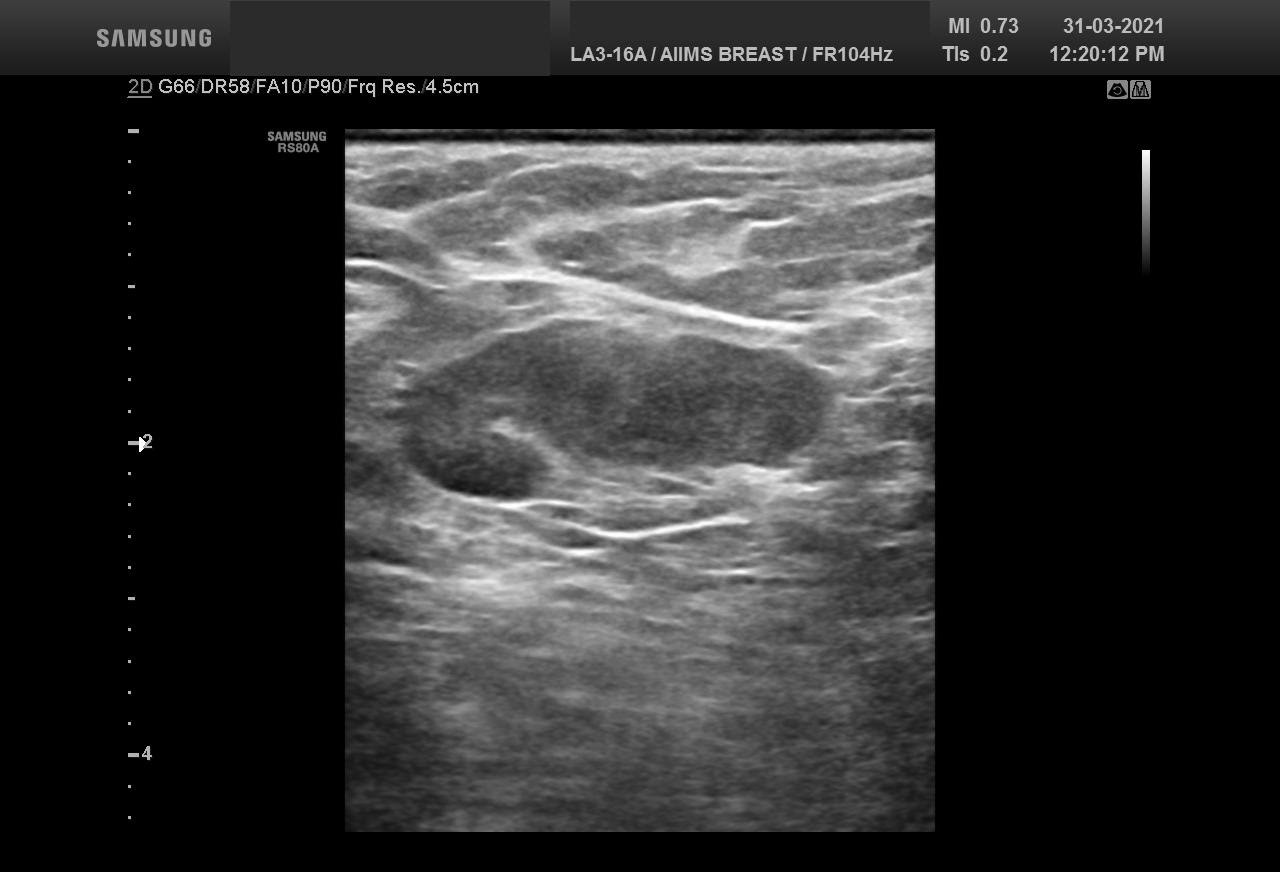

Bilateral Digital mammography , Craniocaudal (CC) and Mediolateral oblique (MLO) view with tomosynthesis images revealed a round shaped, equal density mass with indistinct margin in lower outer quadrant. No suspicious microcalcifications was seen. No significant axillary lymph nodes were present. A high resolution ultrasound of the right breast showed a round shaped, heterogeneously hypoechoic mass with irregular margin, small cystic spaces within and posterior acoustic enhancement, measuring about 1.6x1.9x1.5cm at 7 O’clock position. Mild internal vascularity was noted on colour doppler images. Right axilla showed suspicious lymph nodes with loss of fatty hilum and thickened cortex.

Although the mass has few benign features like round shape and posterior enhancement, presence of irregular margin and axillary nodes with thickened cortex and loss of fatty hilum points towards the suspicious nature of the mass. So, the mass was classified as BIRADS category 4b lesion. Ultrasound guided biopsy of the mass was suggestive of invasive breast carcinoma with possibility of medullary carcinoma. IHC study showed tumor to be Positive for PR and negative for ER and HER2neu receptors. Patient underwent Breast conserving surgery with right axillary lymph node dissection and final histopathological report was Invasive carcinoma with medullary features. Axillary lymph nodes were involved by the tumor.